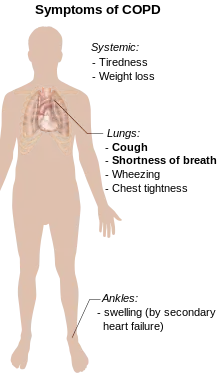

Signs and symptoms

Shortness of breath

A cardinal symptom of COPD is the chronic and progressive shortness of breath which is most characteristic of the condition. Shortness of breath (breathlessness) is often the most distressing symptom responsible for the associated anxiety and level of disability experienced.[4] Symptoms of wheezing and chest tightness associated with breathlessness can be variable over the course of a day or between days and are not always present. Chest tightness often follows exertion.[4] Many people with more advanced COPD breathe through pursed lips, which can improve shortness of breath.[26] Shortness of breath is often responsible for reduced physical activity and low levels of physical activity are associated with worse outcomes.[27][28] In severe and very severe cases there may be constant tiredness, weight loss, muscle loss and anorexia. People with COPD often have increased breathlessness and frequent colds before seeking treatment.[4]

Cough

The most often first symptom of COPD is a chronic cough, which may or may not be productive of mucus as phlegm. Phlegm coughed up as sputum can be intermittent and may be swallowed or spat out depending on social or cultural factors and is therefore not always easy to evaluate. However, an accompanying productive cough is only seen in up to 30% of cases. Sometimes limited airflow may develop in the absence of a cough.[4] Symptoms are usually worse in the morning.[29]

Other conditions

COPD often occurs along with a number of other conditions (comorbidities) due in part to shared risk factors. Common comorbidities include cardiovascular disease, skeletal muscle dysfunction, metabolic syndrome, osteoporosis, depression, anxiety, asthma and lung cancer.[42] Alpha-1 antitrypsin deficiency (A1AD) is an important risk factor for COPD.[43] It is advised that everybody with COPD be screened for A1AD.[42] Metabolic syndrome has been seen to affect up to fifty percent of those with COPD and significantly affects the outcomes.[44] When comorbid with COPD there is more systemic inflammation.[44] It is not known if it co-exists with COPD or develops as a consequence of the pathology. Metabolic syndrome on its own has a high rate of morbidity and mortality and this rate is amplified when comorbid with COPD. Tuberculosis is a risk factor for the development of COPD, and is also a potential comorbidity.[12] Most people with COPD die from comorbidities and not from respiratory problems.[45]

Anxiety and depression are often complications of COPD.[2][1] Other complications include a reduced quality of life and increased disability, cor pulmonale, frequent chest infections including pneumonia, secondary polycythemia, respiratory failure, pneumothorax, lung cancer, and cachexia (muscle wasting).[1][2][46]